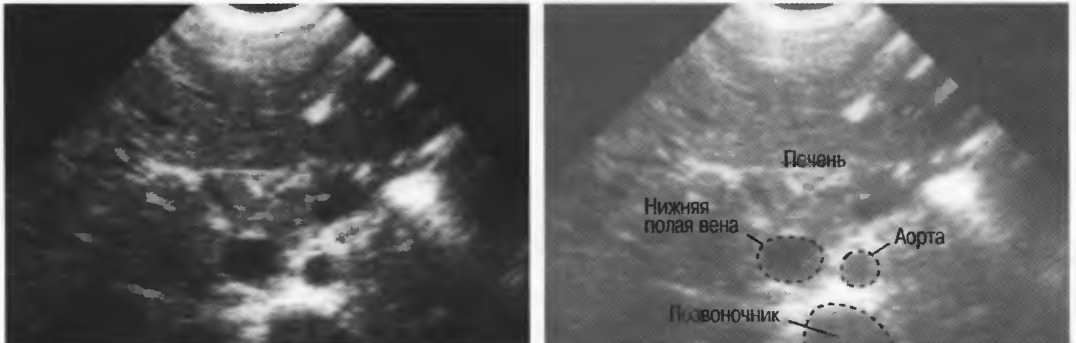

- Печеночные вены диаметром всего 3 мм должны визуализироваться при сканировании под углом 45° к поверхности нормальной печени (рис. 25).

Рис.25. Аппарат хорошего качества должен позволять визуализировать печеночные вены диаметром 3 мм. Этот тест может регулярно использоваться для контроля качества изображения.

4. У здоровых обследуемых паренхима печени должна быть немного более эхогенна. чем кора рядом расположенной почки (рис. 26).

Рис.26. Продольный срез через печень и правую почку: нормальная паренхима печени более эхогенна, чем паренхима нормальной почки. Это еще один способ проверки качества изображения.